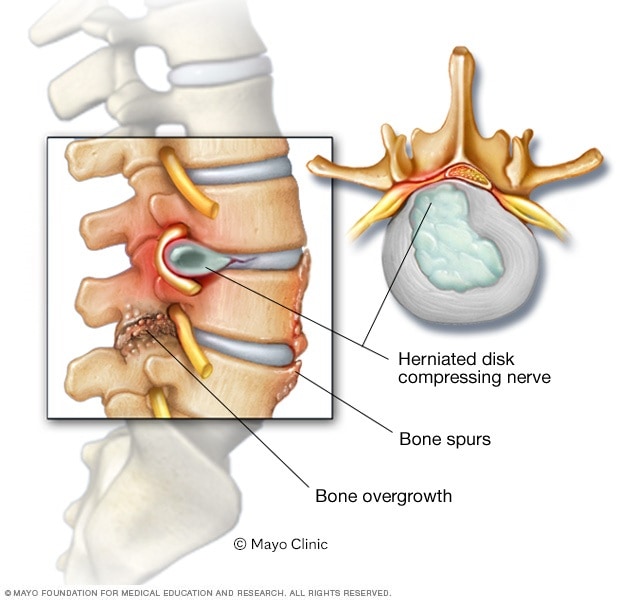

Spinal stenosis – Symptoms and causes – Mayo Clinic

Arthritis (Spine) And Bone Spurs

Low Back Pain and Spinal Stenosis

Foraminal Stenosis of the Spine | Bone Spur | Dr. Donald Corenman …